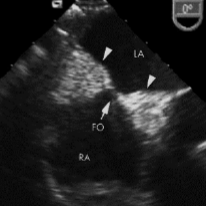

<p>Lipomatous hypertrophy of IAS</p>

Lipomatous hypertrophy of IAS

Normal variant of the heart muscle that can be mistaken for a tumor.

Superior and inferior fatty portions of the IAS sparing the fossa ovalis region.

“Dumbbell” appearance

<p>Normal variant of the heart muscle that can be mistaken for a tumor.</p><p>Superior and inferior fatty portions of the IAS sparing the fossa ovalis region.</p><p>“Dumbbell” appearance</p>

Dumbbell

Lipomatous hypertrophy of the IAS has a characteristic ___ appearance.